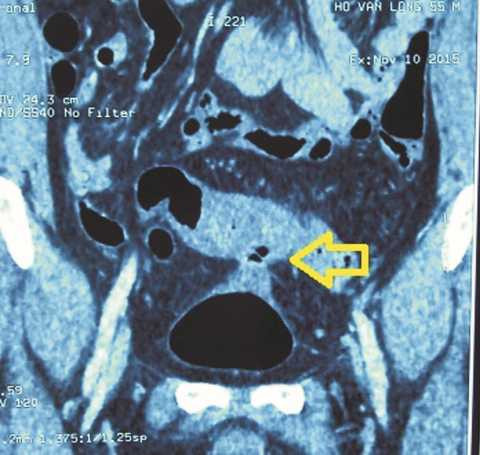

Chụp bàng quang bơm thuốc cản quang tan trong nước thấy thuốc đi vào đại tràng. Chụp đại tràng có thuốc cản quang không tan trong nước thấy thuốc vào bàng quang. Chụp CT bụng phát hiện có khối viêm dính từ đại tràng chậu hông vào bàng quang.

![]() |

| Chụp phim Cystography thấy thuốc ra ngoài bọng đái |